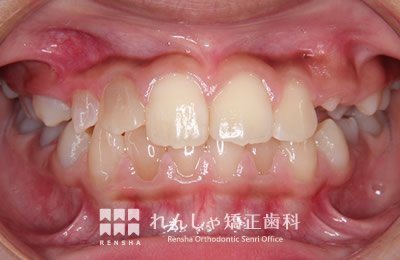

中高生

永久歯列はほぼ完成してしますが、歯列を側方だけでなく後方へも拡大し、埋まっていた右上奥歯を引っ張り出しています。

| 主訴 | 埋まったままでてこない歯がある |

|---|---|

| 診断名 | Angle Class II 小臼歯の埋伏と叢生を伴う上顎前突 |

| 初診時年齢 | 13歳5か月 |

| 装置名 | マルチブラケット装置 |

| 抜歯非抜歯 | 非抜歯 |

| 治療期間 | 2年3か月 |

| 費用の目安 | 約82万円+消費税(検査料金、都度の処置費用等も合わせた総額) |

| リスク副作用 | 歯の移動に伴う軽微な歯根吸収、歯槽骨吸収、歯肉退縮(本症例では軽度の歯根吸収を認めた)、矯正器具装着中のカリエスリスク増大(本症例ではカリエス発生無し) |